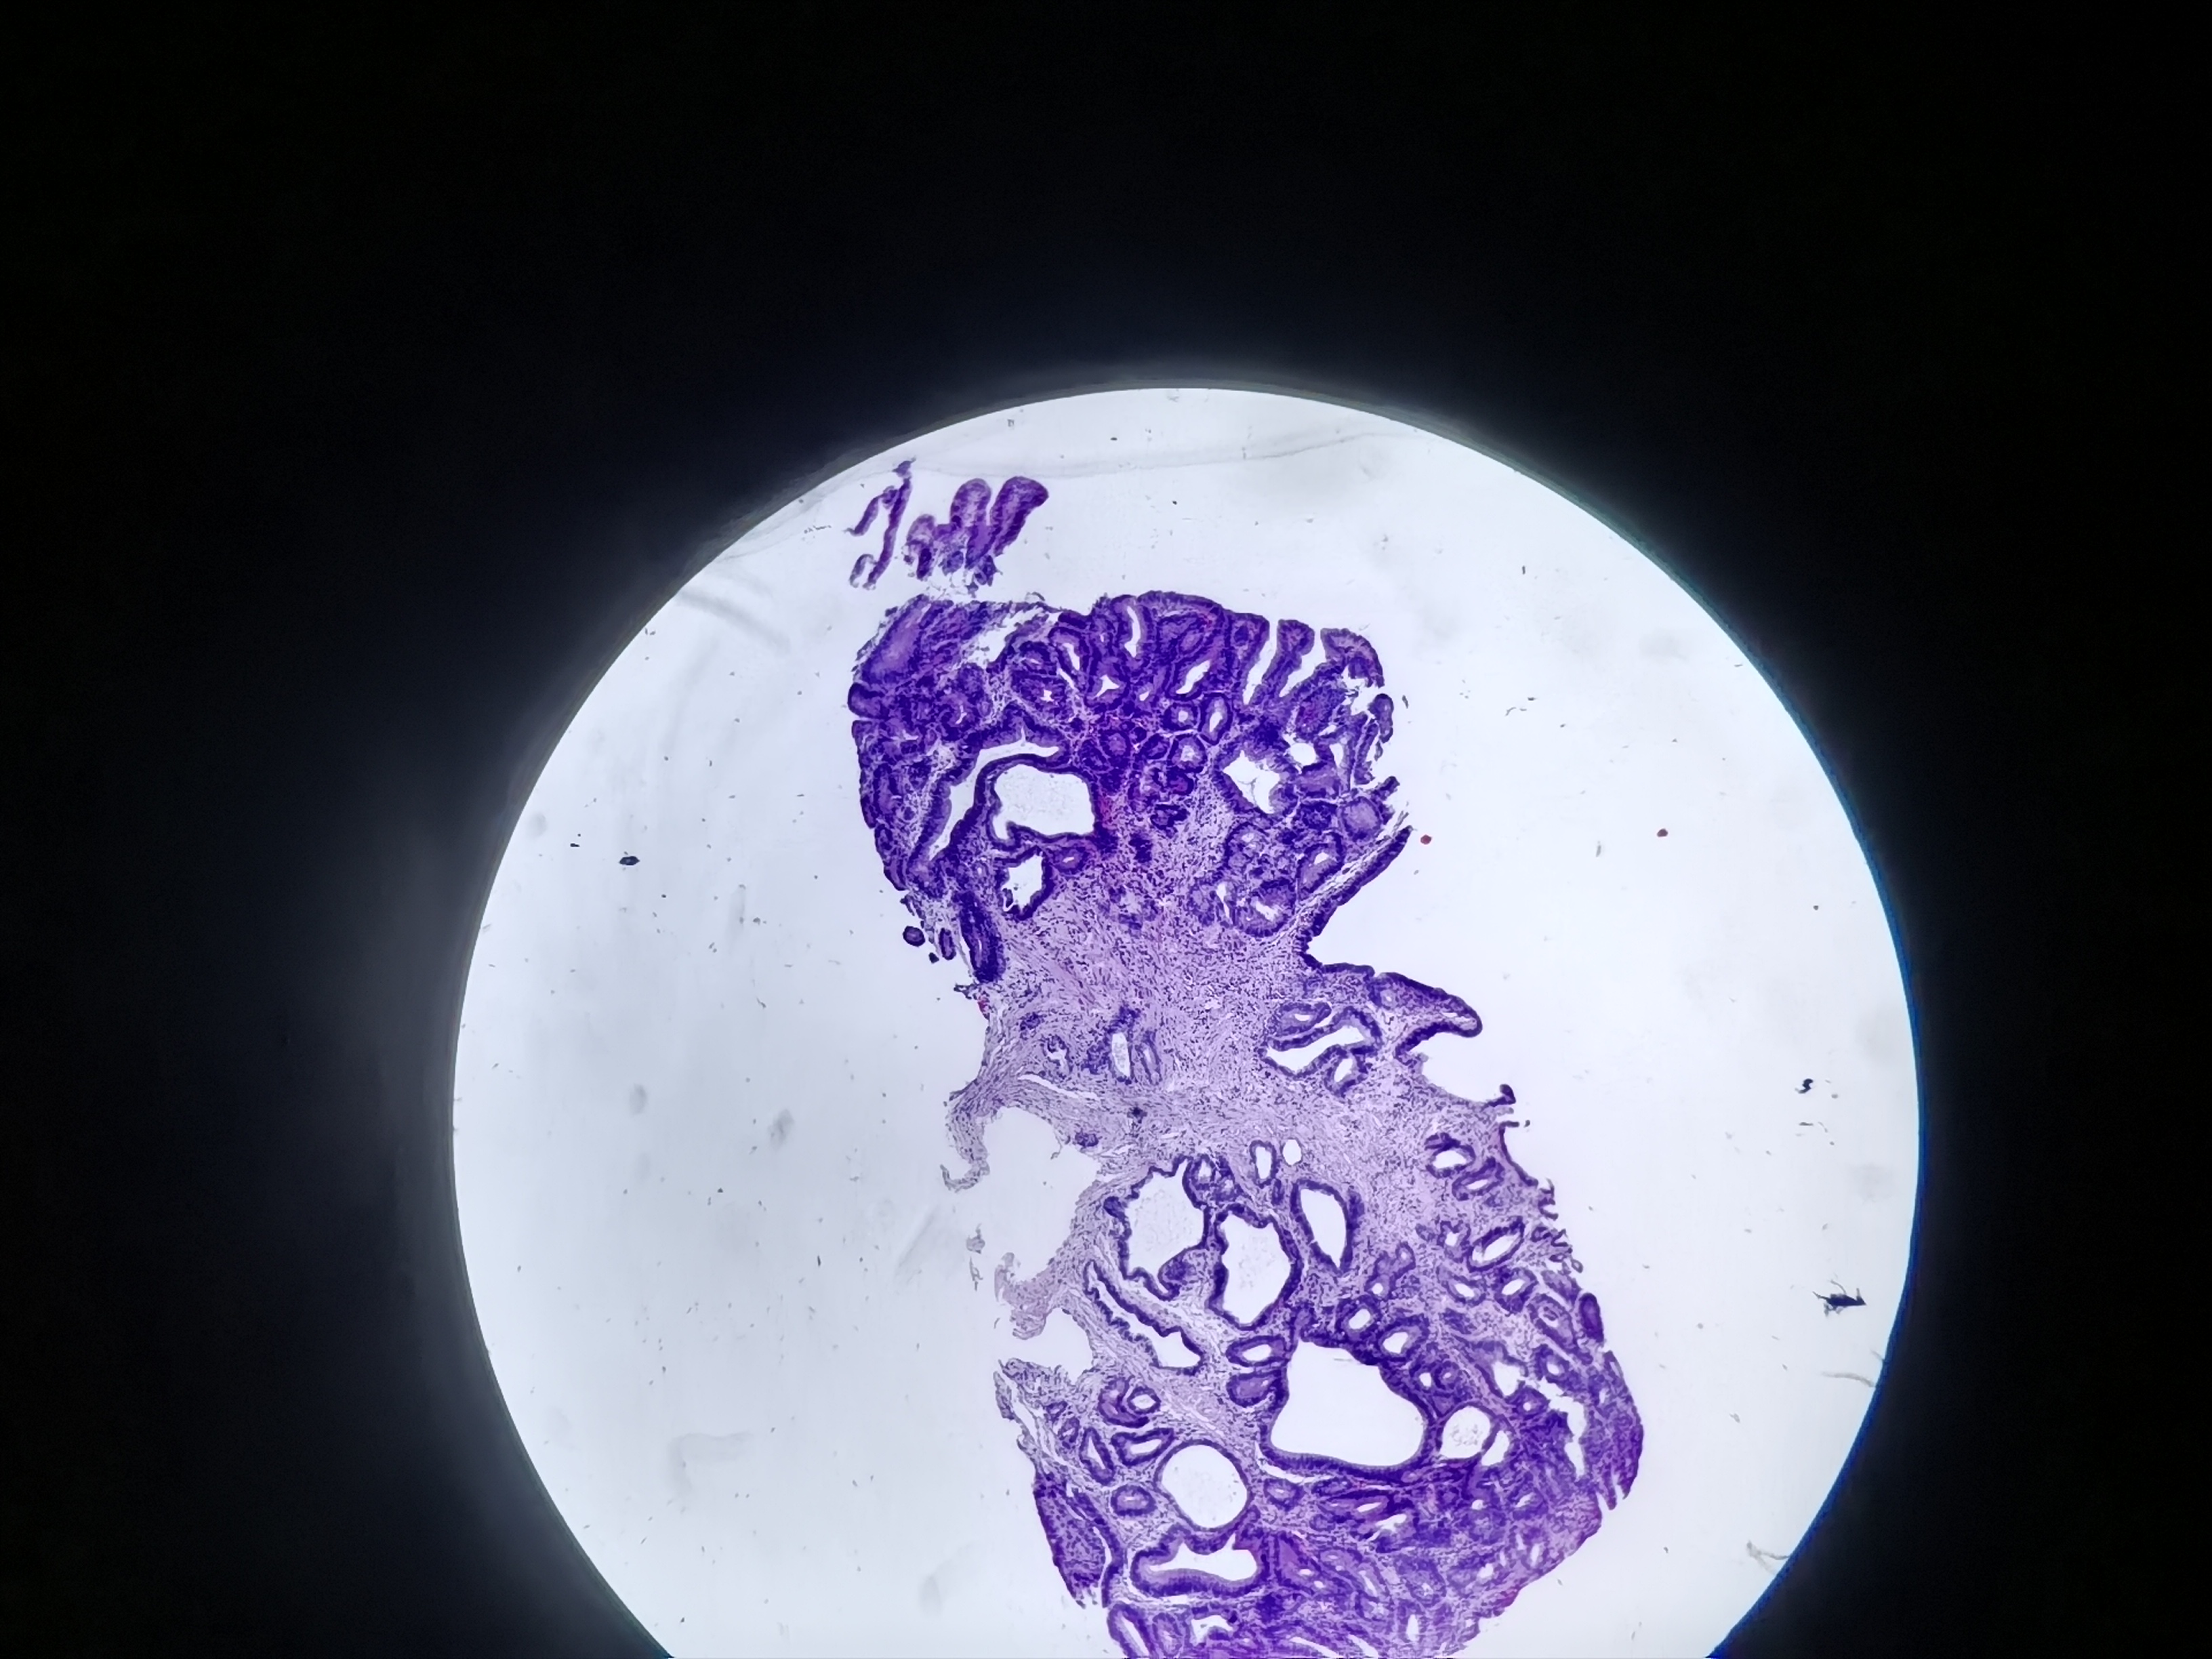

胃角活检

胃角可见粘膜粗糙

胃角粘膜活检

灰白色组织1块

低级别?

图1

低级别

萎缩+肠化+修复